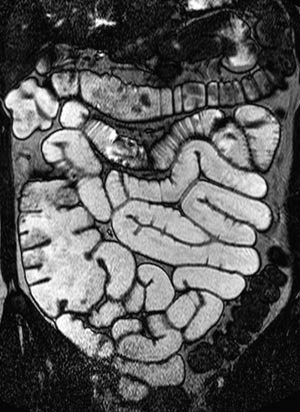

Bruk av sonde gir god utvidelse av både jejunum og ileum (fig 2). Duodenum blir vanligvis ikke fylt med væske fordi sondeballongen hindrer refluks. Av og til vil heller ikke proksimale jejunum bli fremstilt fordi sonden vandrer i distal retning. Den største ulempen med metoden er likevel nedleggelsen av sonden. Pasientene opplever dette som ubehagelig, og prosedyren innebærer fortsatt noe strålebelastning. Det er derfor stor interesse for MR-undersøkelse av tynntarm med oral kontrast.

Vår erfaring med MR av tynntarm med oral kontrast er at metoden gir en god utvidelse av ileum. Bulbus duodeni er også ofte væskefylt, men det er vanskeligere å få resten av duodenum og proksimale jejunum optimalt utvidet (fig 3). En annen ulempe med MR av tynntarm med oral kontrast er ventrikkelretensjon (fig 4). Dette hemmer væskefylling av tarmen, og pasientene kan bli kvalme.